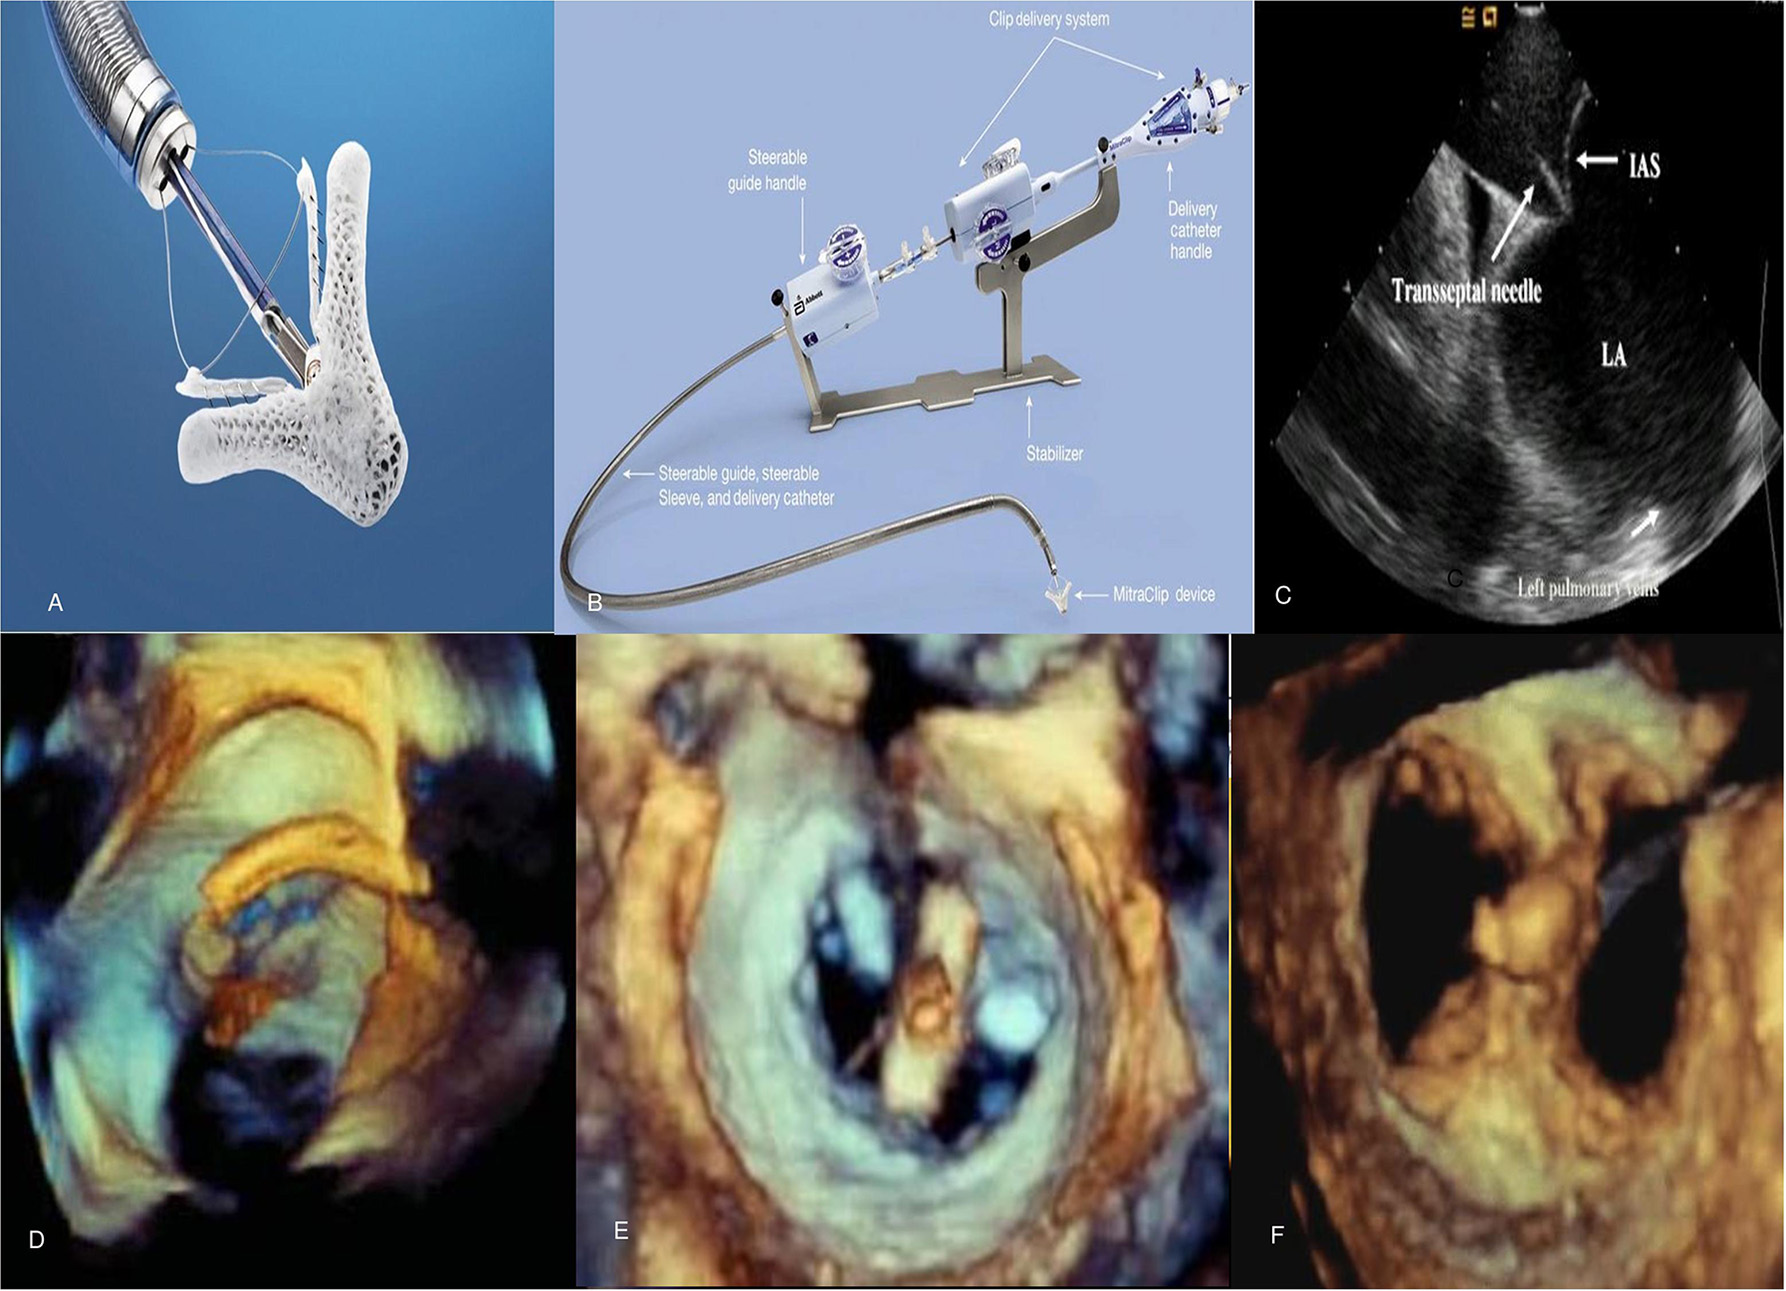

The MitraClip (Abbott Laboratories, Menlo Park, California, USA) is a cobalt chromium clip covered with a polypropylene fabric, has two arms and works by grasping and approximating edges of the anterior and posterior valvular leaflet segments (Figure 4) in patients with severe MR. It is a catheter-based technology that was designed after the surgical Alfieri technique which connects the middle segment of the anterior leaflet to the middle scallop of the posterior leaflet of a regurgitant MV (39). MitraClip received initial CE-Mark approval in Europe in 2008 and was approved by the FDA in 2013 for use in primary MR and 2019 for use in functional MR.

FIGURE 4

Figure 4. Mitraclip system and echocardiographic images during the procedure. (A) MitraClip device has 2 arms and 2 grippers fabricated with metal alloys and polyester fabric. (B) The steerable guide catheter and clip delivery system. (C) Transseptal puncture using intracardiac echocardiography to enter left atrium. (D,E) Stepwise positioning of the MitraClip perpendicular to axis of mitral valve adjacent to the A2-P2 scallops as seen on 3D TEE. (F) Post-MitraClip deployment double-orifice mitral valve seen on 3D TEE. TEE, transesophageal echocardiography.

The percutaneous procedure is performed with the patient under general anesthesia using transthoracic, transesophageal echocardiography and fluoroscopic guidance in the cardiac catheterization laboratory. The MitraClip procedure consists of several steps following femoral venous access [(40); Figure 4]:

1) Transseptal puncture—In primary MR, the puncture site needs to be roughly 5 cm above the mitral annulus to allow sufficient catheter and clip maneuvering. In functional MR the puncture site needs to be more inferior and closer to the annular plane (about 3.5 cm above annular plane) since tethering of leaflets results in coaptation occurring below the plane of the mitral annulus.

2) Advancement of guide catheter and delivery system into the left atrium—A stiff guidewire is passed into the left atrium and the trans-septal apparatus is exchanged for the guide catheter. The clip delivery system is then introduced into the guide catheter and the clip is advanced into the left atrial chamber.

3) Positioning of the MitraClip into the left ventricle to just below the MV leaflets—The clip delivery system is steered until it is aligned over the origin of the regurgitant jet, its arms opened to orient it perpendicular to MV coaptation and advanced into the ventricle just below the leaflet edges.

4) Grasping the leaflet edges, confirming position and releasing the clip—The clip is closed to 120° and pulled back until the mitral leaflets are captured in the arms of the clip. The clip is incrementally closed, while its position, leaflet attachment and the degree of MR can be assessed. Prior to the final release, the clip can be reopened and repositioned if needed. After adequate reduction of MR is ensured, the clip is released from the delivery system and all catheters are withdrawn. In cases with residual MR, additional clips can similarly be placed in the way of regurgitant jets while ensuring no evidence of significant de novo mitral stenosis. The entire procedure is performed on intravenous heparin while serially checking activated coagulation time (goal >250 s). After the clip is placed, patients are treated with aspirin 325 mg daily for 6–12 months and clopidogrel 75 mg daily for 30 days. These recommendations are based on estimated time to device endothelialization.